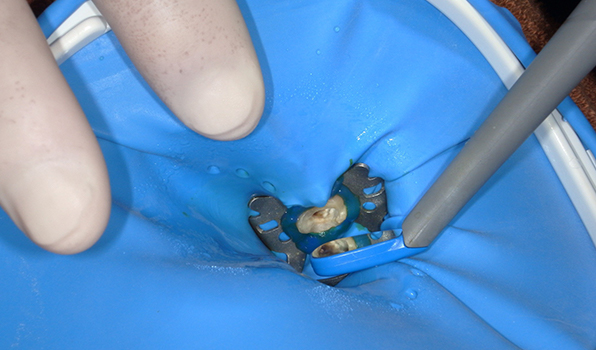

ラバーダム

の使用

根管治療を行う際には、唾液や細菌の侵入を遮断するため、治療する歯を中心にお口全体にゴム製の膜を張ります。

口腔内には多くの細菌が存在しています。治療している歯の中に唾液や細菌が侵入してしまうと、うまく治らなかったり、再治療が必要になることがあります。こうしたリスクをカバーしてくれる他にも、治療の水が喉に流れ込まない、歯の周りを清潔に保つことができる、舌や頬の粘膜を傷つける心配がないなど、ラバーダムには多くのメリットがあります。

根管治療でラバーダムは使いますか?

はい。当院ではすべての根管治療でラバーダムを使用しています。

ただし、ラバーダムだけでは唾液を完全に防ぐことは難しいため、当院ではさらに隔壁とシーリング材(オラシール、デントダム)を併用し、徹底した感染防止を行っています。

さらに、自費診療の患者様には、通常よりも高価な**「オプチダム」**というラバーダムを使用しています。これは口にやさしくフィットし、長時間の治療になる根管治療でも負担が少ないのが特徴です。

患者様に快適に治療を受けていただきたいという思いから、あえて導入している機材です。